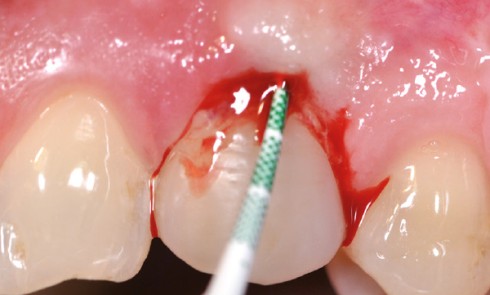

Article réservé à nos abonnés La réintervention endodontique chirurgicale

Le développement des nouvelles technologies endodontiques (limes NiTi rotation continue ou réciprocité…) et des aides visuelles dans nos cabinets permet...